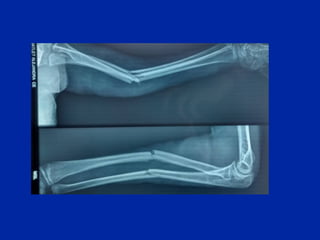

Fracturas del niño

Fracturas en tallo verde Fracturas desplazadas

Fractura poco desplazada. Fractura con desplazamiento importante.